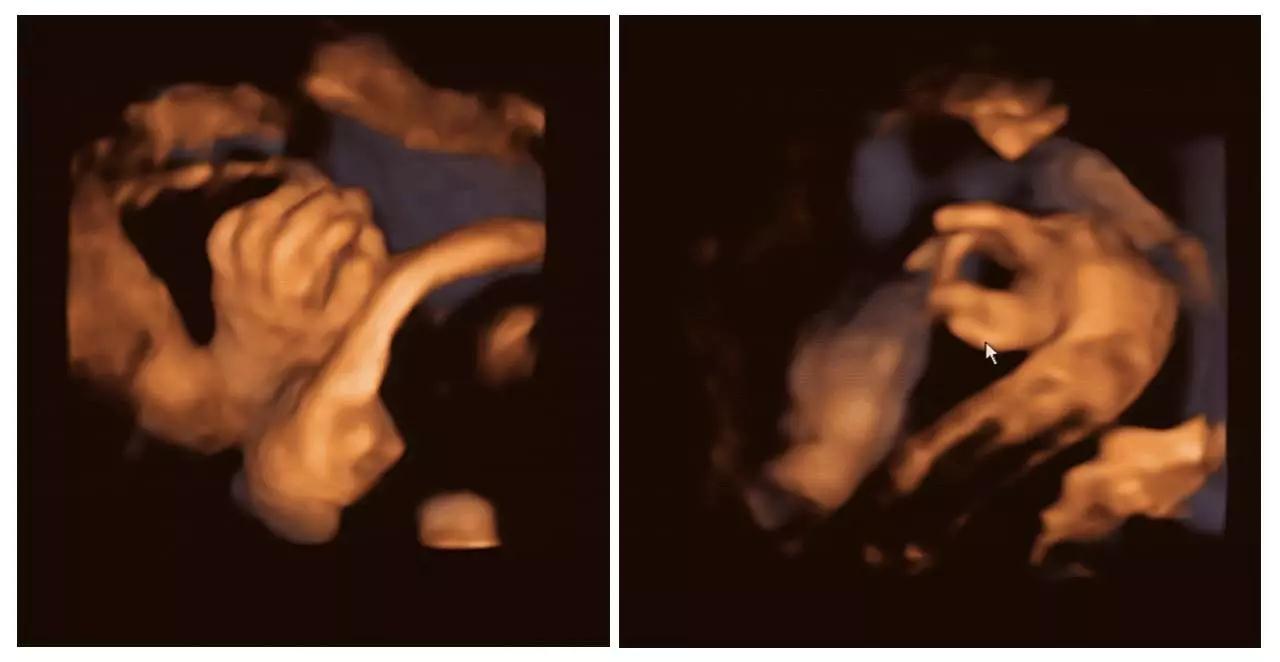

美国GE不仅能提供包括腹部、血管、小器官、产科、妇科、泌尿科、新生儿和儿科等多领域的多方面的应用,而且能够显示未出生的宝宝的实时动态活动图像,为胎儿进行宫内拍“写真”和动态录像,让宝宝拥有最完整的0岁相册。通过四维彩超(四维彩超),可以看到宫内胎儿打哈欠、伸懒腰、吮手指等萌萌的动作,让准爸妈们增添了安心和乐趣,不再仅仅是感觉宝宝的呼吸和运动,可以亲眼目睹宝宝的一举一动和乖巧容颜。还可以打印宫内高清写真,作为送给未来宝宝的珍贵礼物!

(右手多指畸形)